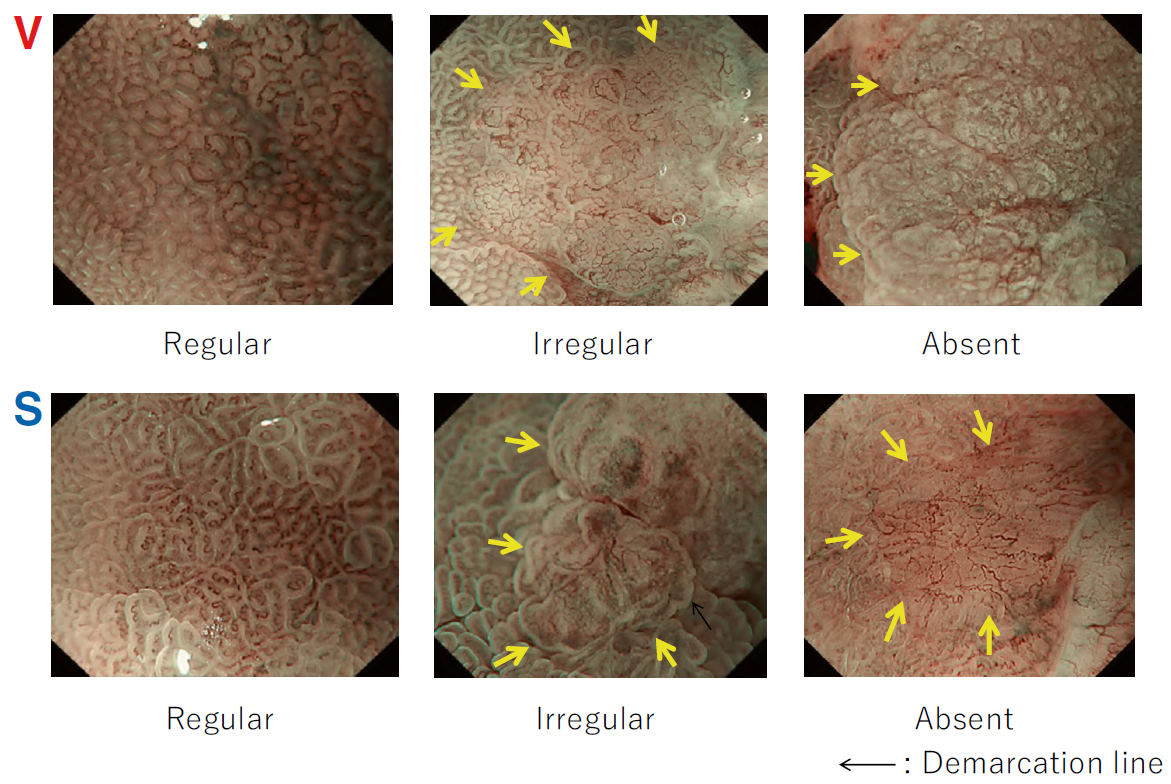

According to the morphology of the anatomical components, the MV and MS patterns were classified as regular, irregular, or absent (. Fig. 2). In principle, the MV and MS patterns must be determined separately.

DL is defined as the border between the lesion and non-lesion areas, discernible through an abrupt change in MV and/or MS patterns (. Fig. 2).

The criteria for high-grade dysplasia (HGD)/early cancer (EC) are as follows:

- Presence of an irregular MV pattern with a demarcation line.

- Presence of an irregular MS pattern with a demarcation line.

A target lesion is diagnosed as HGD/EC if it fulfills both or either of the criteria. If it does not meet either of the criteria, it is diagnosed as noncancerous.